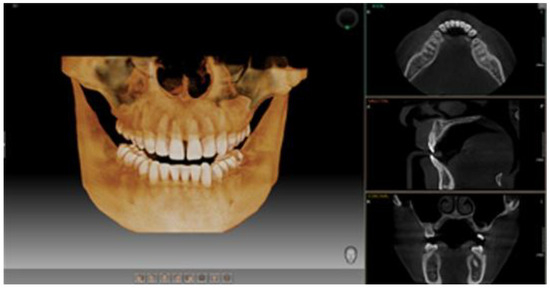

To assess the general and oral health of participants in the two research groups, they completed a personalized questionnaire divided into two sections: general health and oral health. A comprehensive diagnosis included a detailed clinical examination documented with a personalized form numerically correlated to the questionnaire responses, facilitating statistical analysis. CBCT images and clinical results were analyzed by a multidisciplinary team of two dentists and a radiologist. Each CBCT scan was independently reviewed by the dentists, and discrepancies were resolved by consensus to ensure diagnostic accuracy. All patients underwent CBCT imaging using aPaX-i3D device, which provides high-quality 3D images with four selectable fields of view (FOVs), ranging from 5 × 5 cm to 12 × 9 cm. For this study, the 12 × 9 cm FOV highlighted in Figure 1 was used, offering comprehensive coverage of maxillary and mandibular structures, including the wisdom tooth area, ideal for detailed assessment of bone and periodontal lesions. The equipment was provided by Samsung, headquartered at 13, Samsung 1-ro 2-gil, Hwaseong-si, Gyeonggi-do, 18449, Korea

Figure 1. Representative image of the 12 × 9 cm field of view (FOV) obtained through CBCT.